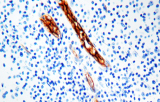

- Linfoma di Hodgkin classico: le cellule tumorali sono tipicamente CD30+ e spesso CD15+, con PAX5 debole e CD20 negativo nelle grandi cellule tumorali.